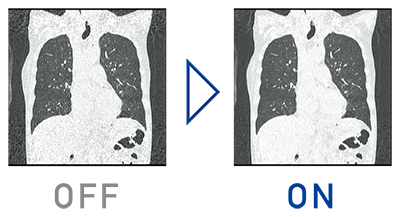

特長<1>

逐次近似処理をルーチン検査に

逐次近似処理をルーチン検査で使いやすくする為に,画像処理速度を50%向上させ,ノイズ低減の強度も7段階から選択できます。適切な被ばく線量と,画像ノイズなどの低減による高画質な画像を提供します。